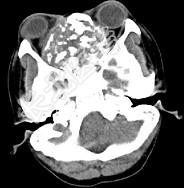

- 多项选择题男性,28岁, 因鼻塞、头痛1年余,鼻窦CT扫描如图所示, 请选择正确的描述与结论 ( )

A、双侧上颌窦、筛窦、鼻腔及蝶窦内见软组织肿块影

B、肿块内密度不均,有较多致密钙化影

C、窦壁及颅底骨质破坏